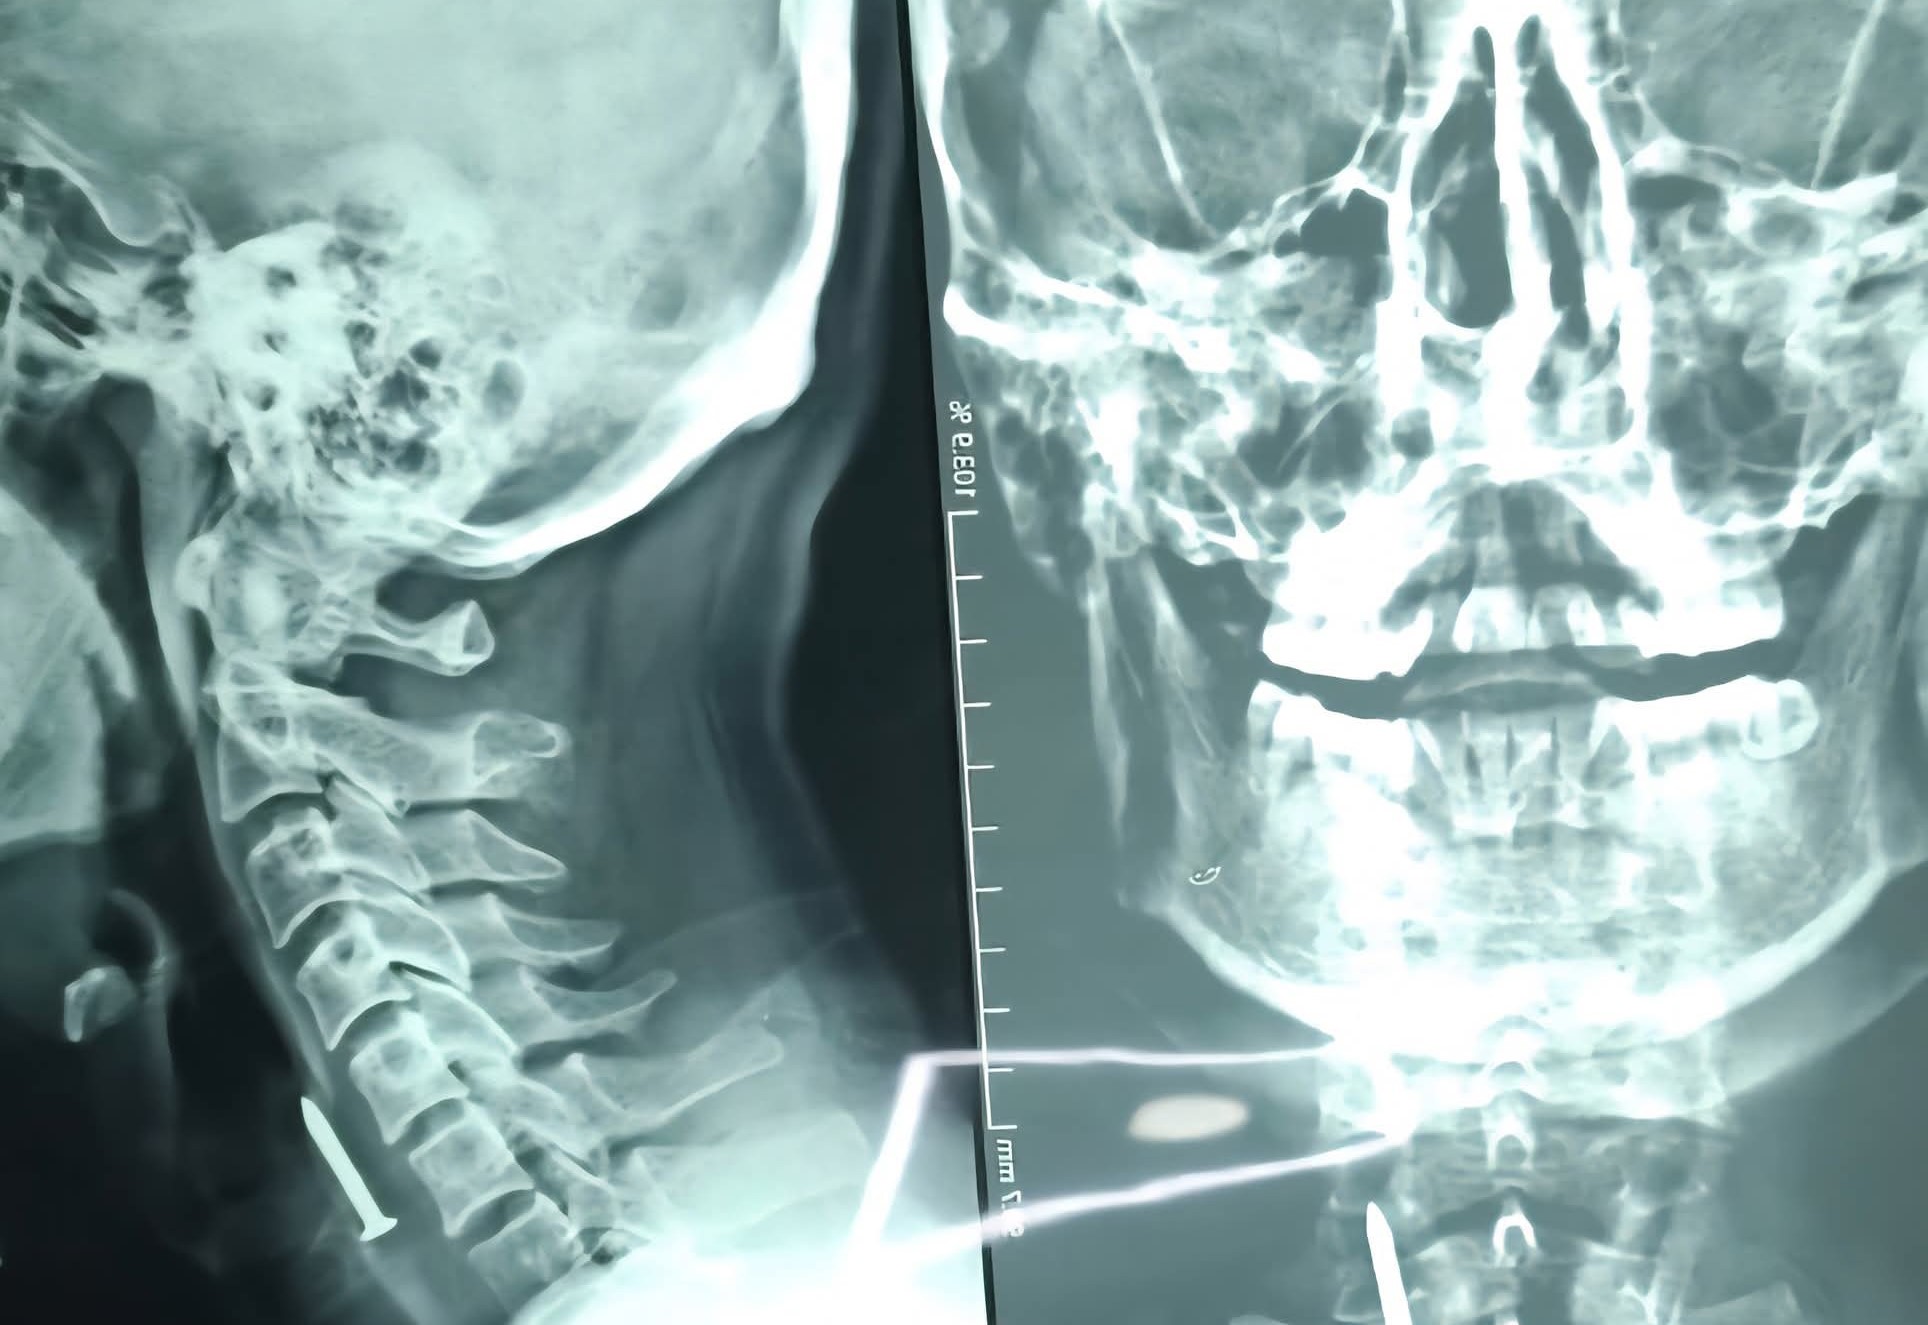

لەلایەن تیمی ئێشكگری نەخۆشخانەی كۆئەندامی هەرس و جگەری فێركاری لەشاری سلێمانی بزمارێك لە گەرووی چارەخوازێكی تەمەن 36 ساڵ دەرهێنرا و توانرا ژیانی ڕزگاربكرێت.